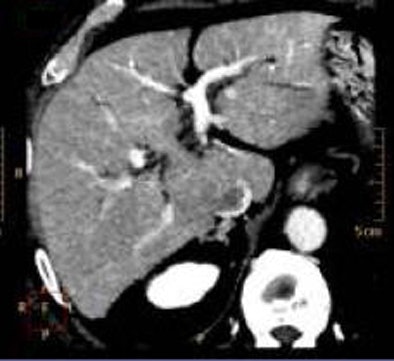

In contrast, the iDose algorithm (Philips Healthcare, Andover, MA) that Mendel described in his ISCT talk uses an iterative method designed to reproduce the look of full-dose filtered back projection (FBP) at a much lower dose using an iterative method. The goal is to allow use of a higher percentage of iterative reconstruction while maintaining a clinically acceptable image.

First, the projection data itself are denoised with the application of a Poisson denoising algorithm. Then in the pixel space, iDose compares the image to a noiseless ideal anatomical model, enabling noise reduction with an appearance that is very similar to the full-dose image and does not shift the noise spectrum significantly, Mendel said.

"So even at 80% dose reduction, the images are virtually identical" to a full-dose image, even when the images are rendered, he said. In contrast, the first-generation systems show major shifts in the noise spectrum, sharpening edges and blurring other structures compared to standard images.

The key aspect of iDose is that it maintains the noise power spectrum (thus the appearance) of a full-dose image while utilizing high levels of dose reduction, Mendel said.